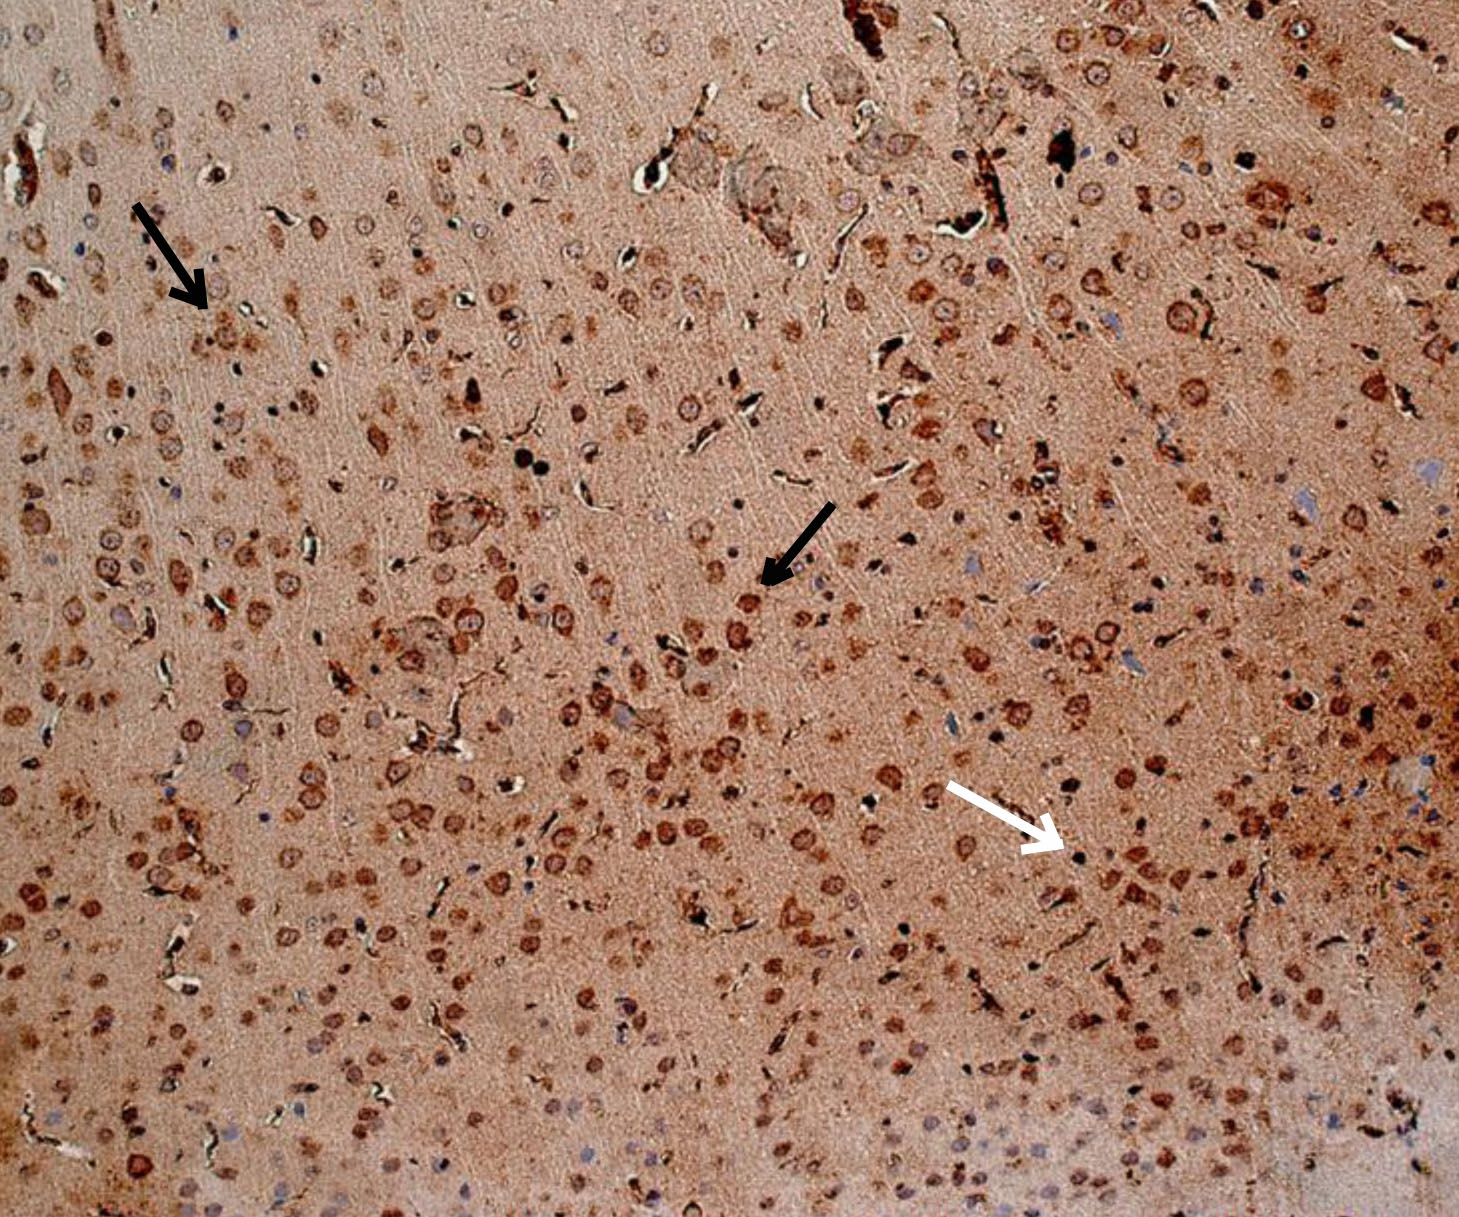

Рис. 2. Животное с СД1 без лечения (физраствор) – выраженная экспрессия ИРМ IL-6. Иммуногистохимическое исследование, антитела против IL-6. Увеличение ×200. Черные стрелки – экспрессия в неповрежденных нейронах. Белые стрелки – экспрессия в нейропиле

При оценке результатов ИГХ исследования коры 19-месячных крыс без СД (интактных) была выявлена слабая равномерная экспрессия ИРМ IL-6 во всех слоях первичной и вторичной соматосенсорных областях коры головного мозга. В моторной, а также ретроспленальной коре была обнаружена цитоплазматическая экспрессия IL-6 в перикарионах нейронов от слабой до умеренной степени. У отдельных животных отмечалось наличие умеренной экспрессии IL-6 в базальных отделах коры. Преимущественно экспрессия ИРМ IL-6 определялась в цитоплазме неповрежденных нейронов, реже в нейропиле. В группе животных с экспериментальным СД1 без лечения наблюдалось увеличение выраженности экспрессии ИРМ IL-6 от умеренной до выраженной степени в сравнении с группой 19-месячных животных без СД. Характер экспрессии схож с характером экспрессии у 19-месячных животных без СД. Цитоплазматическая экспрессия ИРМ IL-6 также наблюдалась в моторной и ретроспленальной коре, локализация ИРМ IL-6 определялась в перикарионах нейронах пирамидного, внутреннего зернистого, ганглиозного слоев и в микроглии. В группах фармакокоррекции сукцикардом и аминалоном в сравнении с группой животных с СД1 без лечения наблюдалось снижение выраженности экспрессии во всех областях коры головного мозга, а в базальных отделах вплоть до исчезновения ИРМ IL-6 (рис. 1–4).